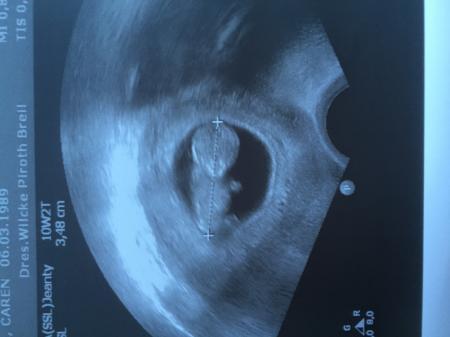

Huhu! :) Tolles Bild! Ich war am Montag beim Arzt! Bin auch in der 11. SSW! Heute 10+4! Meine Übelkeit wurde ab der 10. SSW besser! Ist aber noch nicht ganz weg! An dem einen Tag mehr, an dem anderen weniger! Hier ist unser Bild :-)

Bild zu